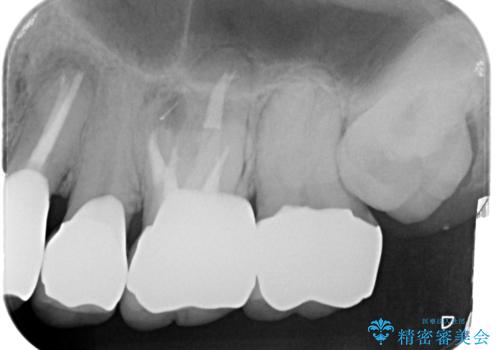

- 銀歯・虫歯・治療途中の歯を治していきたい、セラミックの歯にしたい!と希望され来院されました。

銀歯の下で再発した虫歯や、根尖病変等、多々の問題が認められましたがひとつづつ丁寧に改善し、長期的な予後の見込めるセラミック治療を行っていきます。

適合の良いセラミック治療をおこなったことで、歯ブラシがしやすくなり銀歯の見た目だけでなく歯ぐきの状態も大幅に改善することができました。